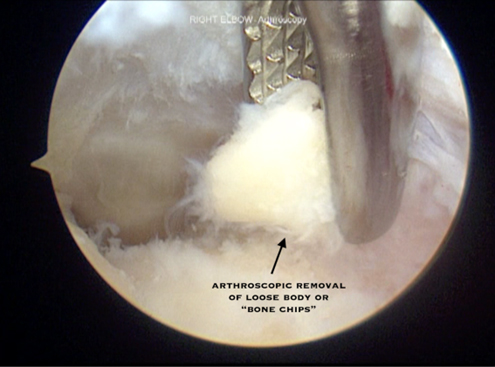

- Arthroscopic resection of osteophytes and removal of loose bodies is indicated for throwing athletes who have failed to improve or have ongoing mechanical symptoms

- Care must be taken to only remove posteromedial osteophytes and avoid over-resection as this can lead to increased stress on the ulnar collateral ligament resulting in valgus instability